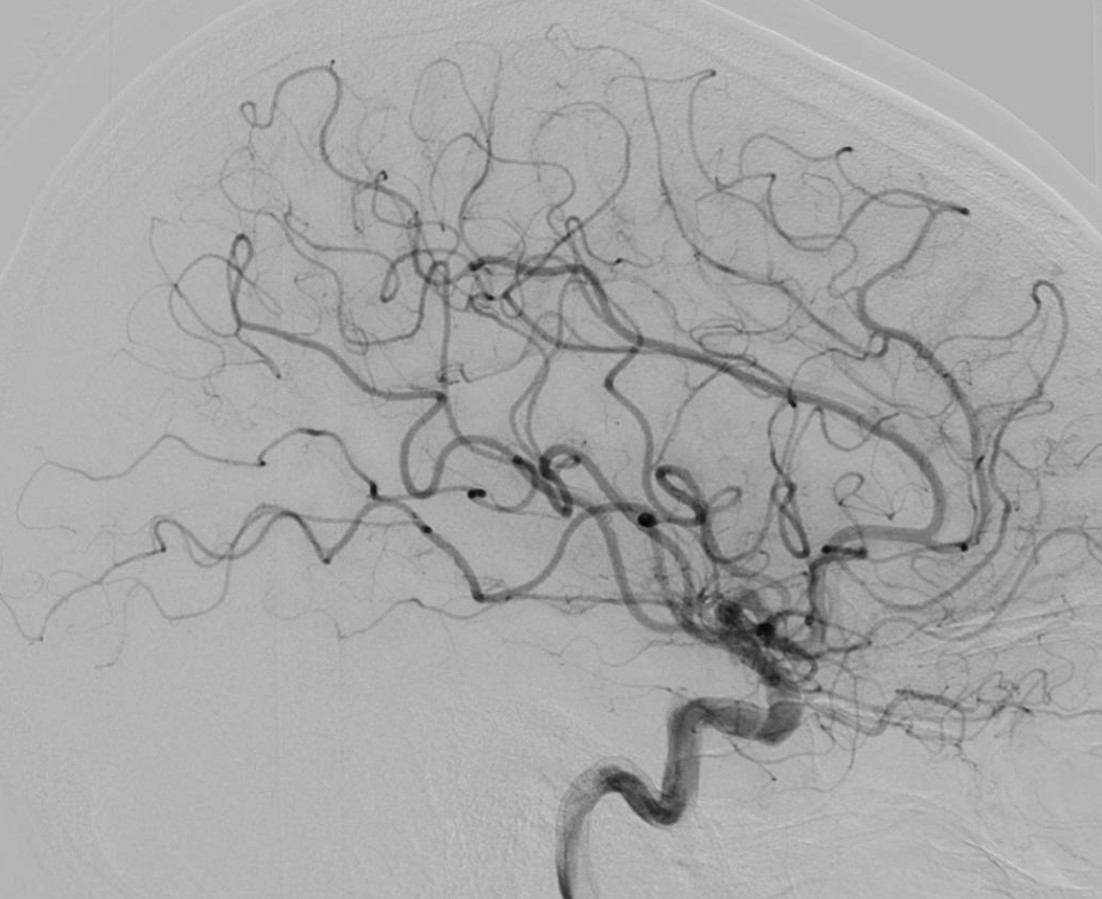

L’artériographie cérébrale, ou angiographie cérébrale, est une technique d’imagerie médicale diagnostique invasive qui permet de visualiser les vaisseaux sanguins du cerveau. Elle consiste à injecter un produit de contraste iodé directement dans les artères, via un cathéter (petit tuyau), ce qui rend les vaisseaux visibles par les systèmes d’imagerie à rayons X. Cette procédure est réalisée par un neuroradiologue interventionnel et permet d’obtenir des images très détaillées du réseau vasculaire cérébral.

L’artériographie cérébrale est utilisée pour diagnostiquer des pathologies vasculaires, tels que les anévrismes intracrâniens, les malformations ou fistules artério-veineuses, les vascularites et les sténoses artérielles. Il s’agit d’un acte interventionnel à visée diagnostique. L’extrême précision des images permet aux médecins de comprendre en détail et en 3D l’état vasculaire du patient et de décider des meilleures options de traitement.

L’artériographie cérébrale est la méthode la plus précise et l’examen de référence pour diagnostiquer les pathologies des vaisseaux sanguins du cerveau. Elle permet un diagnostic détaillé des affections vasculaires cérébrales, bien plus fin que d’autres techniques d’imagerie comme l’IRM ou le scanner. Grâce à sa haute résolution spatiale, elle est particulièrement efficace pour guider les traitements, comme l’embolisation d’un anévrisme.